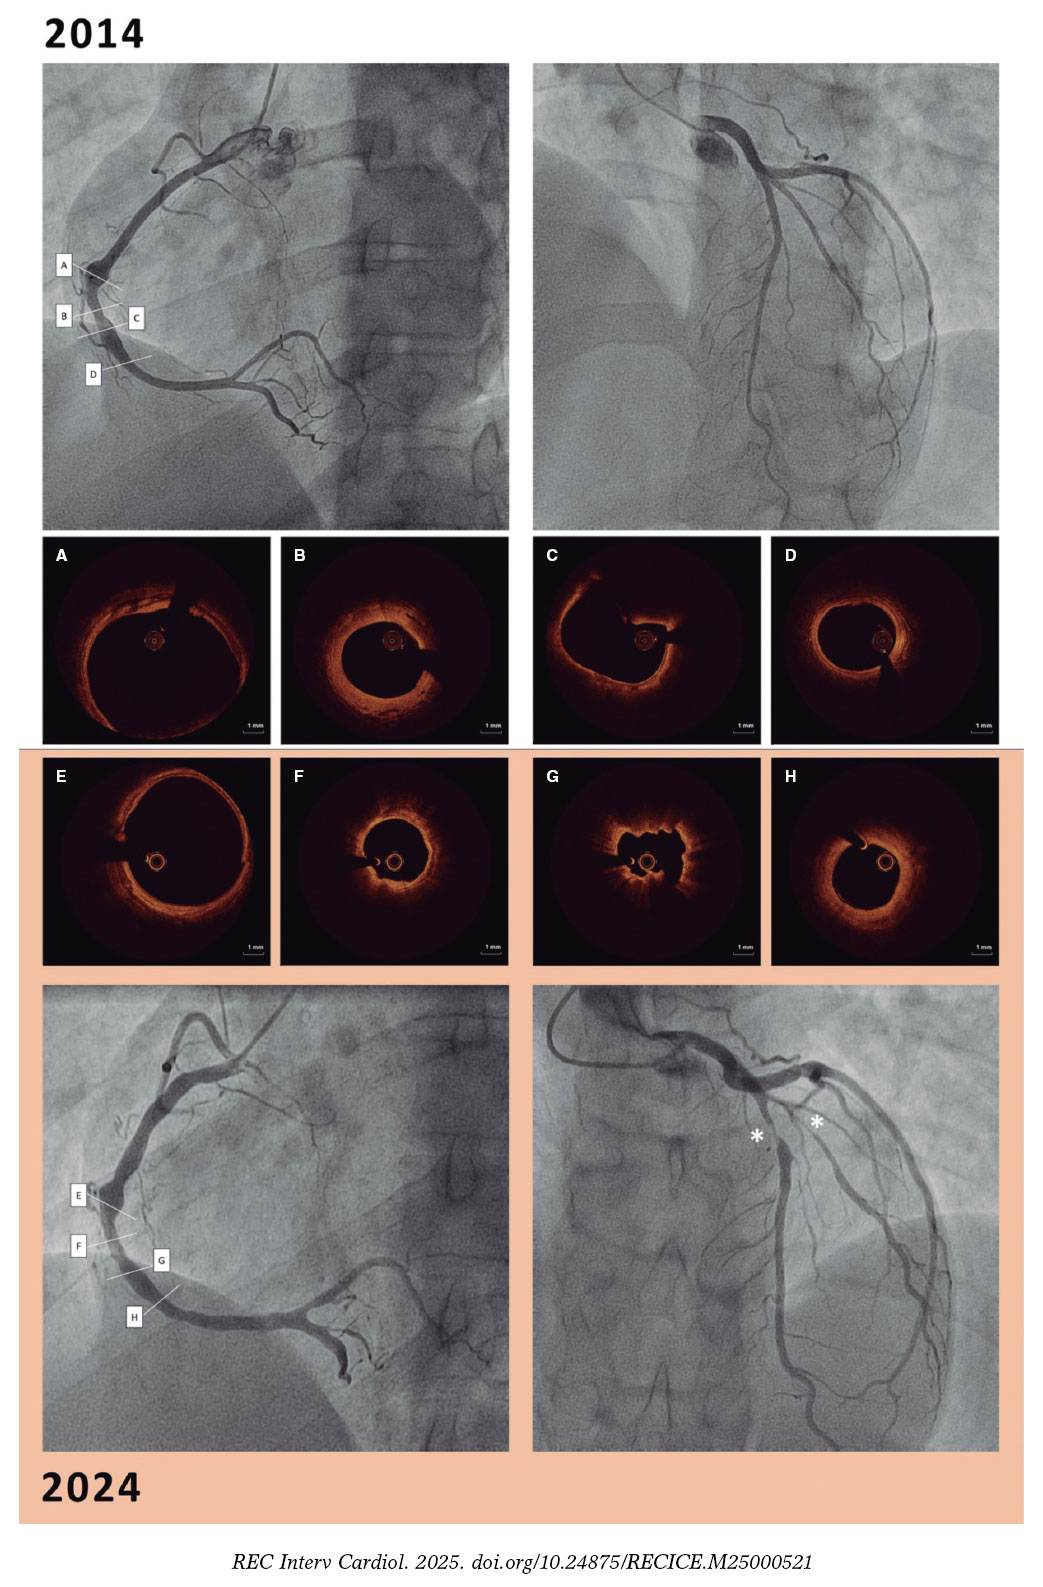

Based on the symptoms and left anterior descending coronary artery findings (intimal thickening and medial disruption, suggestive of vasculitis; figure 3A, asterisk and arrow), with a healthy distal vessel (figure 3A, double asterisk). A transcatheter coronary intervention with drug-coated balloon was performed (figure 3B).

Figure 3.